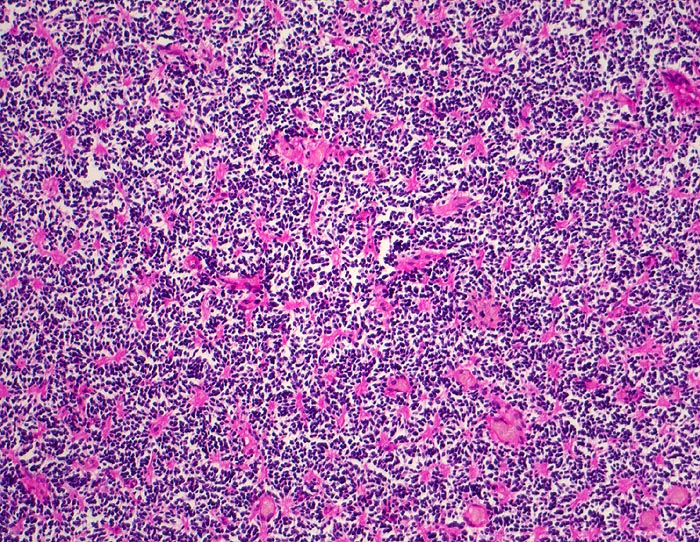

Medulloblastom: Homer Wright Rosetten

Diagnose Gruppe

maligner Tumor

Kleinhirn

Nervensystem

Monomorpher Zellrasen mit hyperchromatischen Zellen ohne erkennbares Zytoplasma. Multiple

Homer Wright Rosetten erkennbar am eosinophilen Zentrum aus Zellfortsätzen.

Knabe mit Kopfschmerzen und morgendlichem Erbrechen ohne Übelkeit

Histologie

100